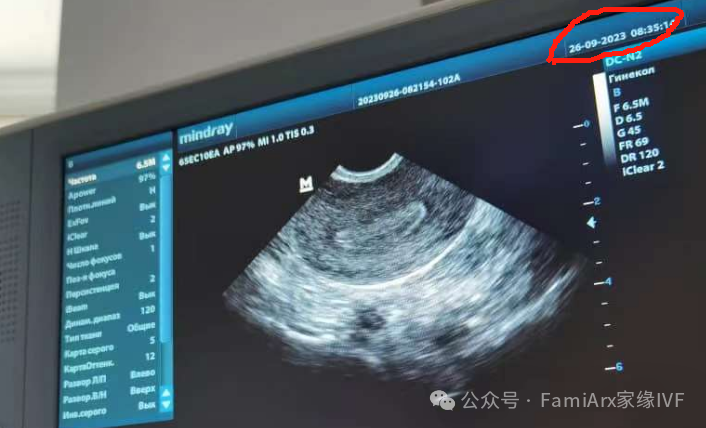

我还有着她第一次做B超检查子宫的视频

然后我们在10月23号,以10mm的很好的内膜指标进行了移植。